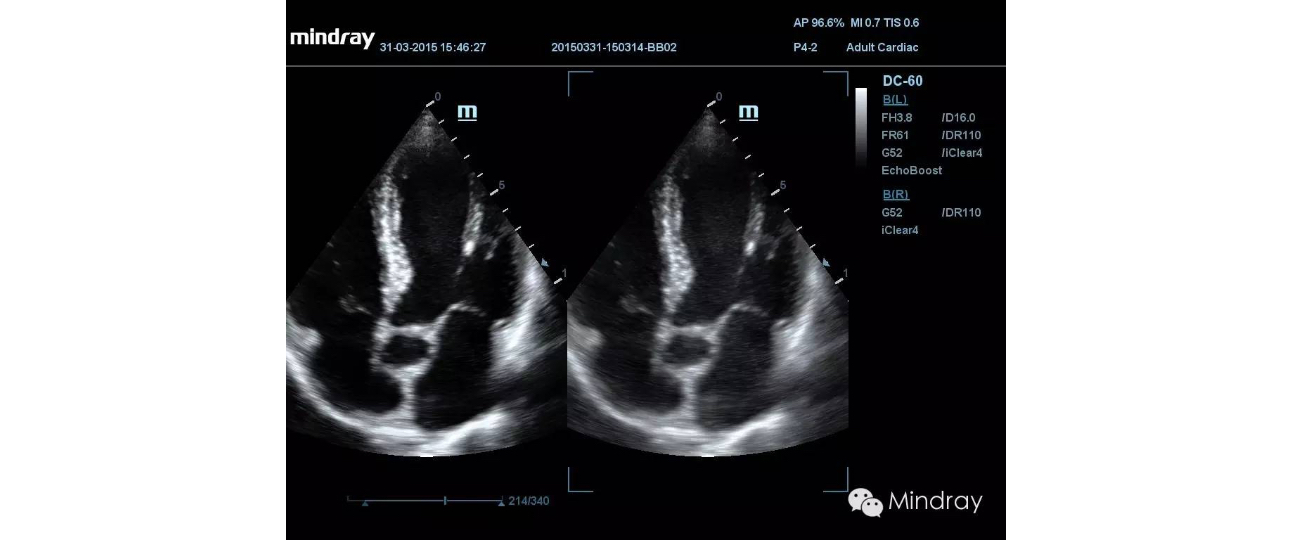

Echo Boost on / off

pc23-s3-2@web